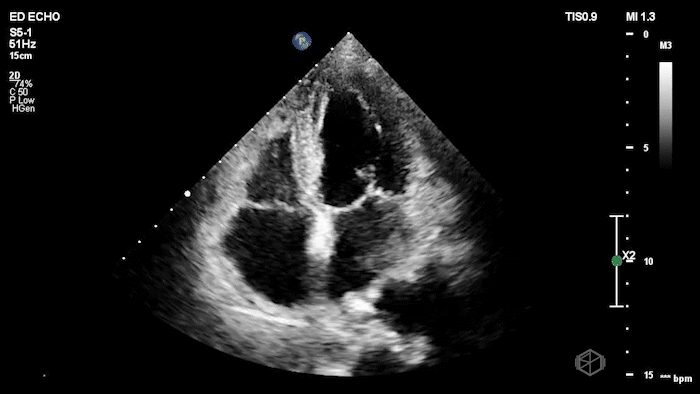

01 - What is the concerning finding and what is the differential?

Mitral valve mobile echogenic mass concerning for endocarditis, patient found to have MV endocarditis.